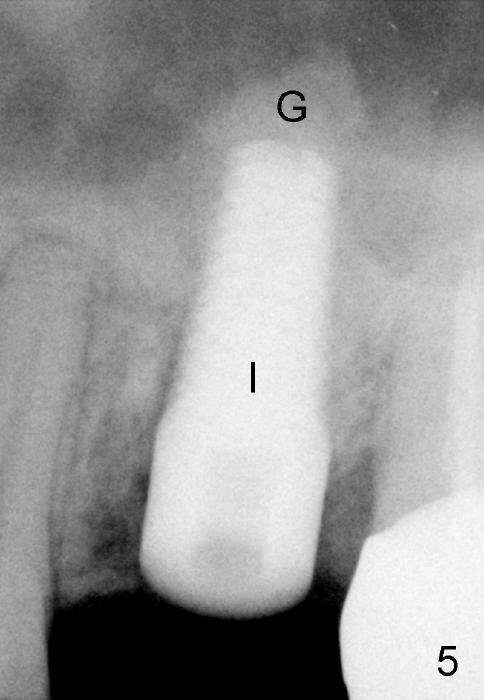

Mixture of autogenous bone from reamer, allograft and synthetic bone is placed in the mesiobuccal and palatal sockets before placement of the 6x17 mm implant (Fig.5 I).  Unfortunately some of graft blocks the apical osteotomy.  To clear the blockage, some of previous osteotome and taps are re-inserted.  The result is in fact beneficial, as bone graft (G) is pushed upward.